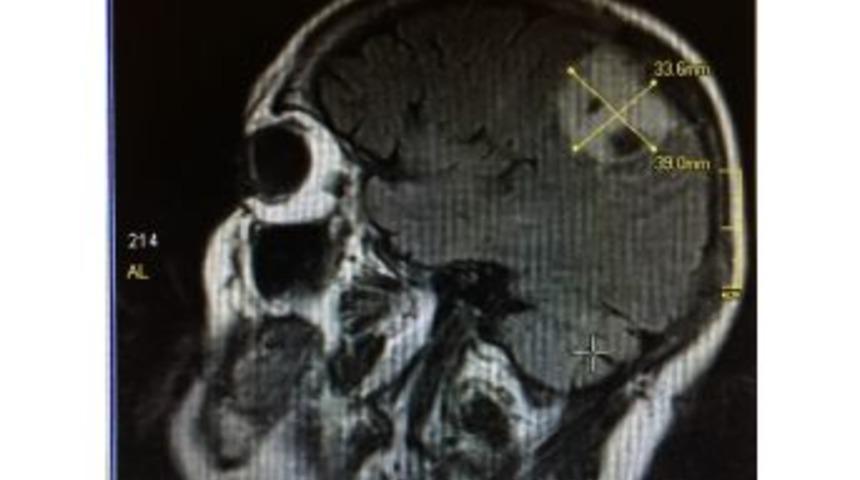

Antalya’da 76 yaşındaki kadının beynindeki mandalina büyüklüğündeki tümör, hasta bayıltılmadan gerçekleştirilen 4 saatlik operasyonla alındı.Antalya’da yaşayan 76 yaşındaki Zaibat Konuk, 10 yıl önce baş dönmesi şikayetiyle gittiği hastanede beyninde tümör olduğunu öğrendi. Konuk, cerrahi operasyonun riskli olduğunun söylenmesi üzerine ameliyat olmaktan vazgeçti ancak tümör her geçen gün büyüyerek mandalina boyutuna ulaştı. Şiddetli baş ağrıları çekmeye ve denge sorunu yaşamaya başlayan Konuk, geçen hafta Medisu Hastanesi’ne başvurdu. Yapılan tetkiklerin ardından Konuk’un ameliyat olmasına karar verildi.Beyin ve sinir cerrahi uzmanı Op. Dr. Ümit Özkan tarafından önceki gün ameliyata alınan Zaibat Konuk’a, Türkiye’de nadir yapılan bir beyin cerrahi operasyonu gerçekleştirildi. “Uyanık anesteziyle beyin ameliyatı” adı verilen yöntemle 6x7 santimetre çapındaki tümör, hasta ile konuşa konuşa alındı. Yaklaşık 4 saat süren operasyonun ardından hasta yoğun bakımda kalmadan servise çıkarıldı. Sağlık durumu iyi olduğu belirtilen Konuk’un yarın taburcu edileceği açıklandı.UYANIK ANESTEZİYLE BEYİN AMELİYATIHastanın durumuyla ilgili bilgi veren Op. Dr. Ümit Özkan, “Hastanın beynindeki tümör yaklaşık 10 yıl önce tespit edilmiş. Cerrahi önerilmiş ancak ameliyat olmamış. Bize başvurana kadar tümör daha da büyümüş. Vücudun sol tarafında kuvvetsizlik ve hissiyatsızlık başlamış. Tümör sadece beynine değil, beyin zarına ve kafatasına da zarar vermiş. Ağrıları dayanılmaz bir boyuta ulaşınca bize başvurmuş. Tümör beyindeki kontrol merkezine yerleştiği için uyanık anesteziyle beyin ameliyatı yapmaya karar verdik” dedi.AMELİYAT ESNASINDA KOMUT VERİLDİOperasyonu hasta ile konuşa konuşa gerçekleştirdiklerini anlatan Op. Özkan şunları söyledi:“Normal ameliyatlarda hasta ameliyathaneye alındıktan sonra solunum cihazına bağlanır ve genel anestezi uygulanarak uyutulur. Bu yöntemde ise hastaya birtakım özel ilaçlar vererek hafif bir uyku hali oluşturduk. Tümörü çıkarırken belli aşamalarda kolunu hareket ettirmesi, kaldırması ve elini sıkması gibi komutlar verdik. Bir taraftan da konuşarak konuşma merkezini takip ettik. Hastanın hareketlerini kontrol ederek tümörü, beyin zarını ve kafatasını çıkardık. Yapay beyin zarı ve yapay kafatası ile ameliyatı sonlandırdık.”AMAÇ BEYNE ZARAR VERMEMEKYöntemin amacının beyne zarar vermeden tümörün çıkarılması olduğunu belirten Op. Dr. Özkan, “Genel anestezi ile yapılan operasyonda hastaya bir zarar verdik mi vermedik mi bilemeyiz ancak uyandıktan sonra tetkiklerini yapıp bunu anlayabiliriz. Zarar görmüşse iş işten geçmiştir. Bu ameliyatın en büyük avantajı, tümörü çıkarırken aşama aşama ilerliyoruz. Zarar gördüğünü hissettiğimiz anda durup taktiğimizi değiştiriyoruz. Örneğin kolunu kaldır dedik ve zorlanmaya başladı. O noktada tümörü çıkarırken biraz daha dikkatli olup agresif davranmadan merkezi korumaya yönelik hareket ediyoruz” diye konuştu.HASTALAR YOĞUN BAKIMDA KALMIYORYöntemin hastalara da büyük avantaj sağladığını ifade eden Op. Dr. Ümit Özkan, “Hasta genel anestezinin olumsuzluklarından kurtulmuş oluyor. Yürüyerek girdiği ameliyathaneden konuşarak çıkıyor. Yoğun bakım süreci yaşamıyor. Böylece hastanede kalış süreleri de kısalıyor. Hastamızı ameliyatın üçüncü gününde taburcu edebiliyoruz. Zaibat Konuk’un da sağlık durumu oldukça iyi ve taburcu şamasına geldi” dedi.“TUHAF BİR DUYGUYDU”Beynindeki tümörden 10 yıl sonra kurtulan 3 çocuk ve 3 torun sahibi Zaibat Konuk ise, “Riskli olduğu söylenince ameliyat olmak istemedim. Son zamanlarda artık yürümekte zorlanınca ve şiddetli ağrı çekmeye başlayınca hastaneye başvurdum. Doktorum uyanık olarak ameliyat olacağımı söyleyince şaşırdım ama korkmadım. Ameliyat olurken kendimdeydim. Her şeyi hatırlıyorum. Ameliyat esnasında doktorumla konuşmak tuhaf bir duyguydu. Sağlığıma kavuştuğum için çok mutluyum” ifadelerini kullandı.